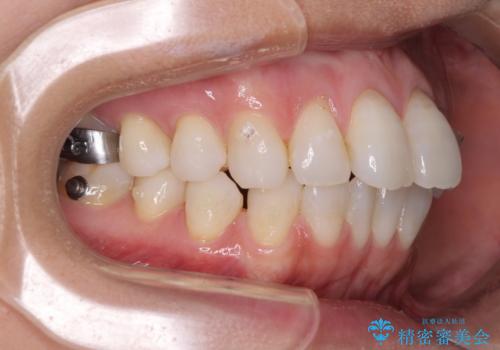

少しだけ飛び出た前歯を整えたい インビザラインによる矯正治療

- 少しだけ前に飛び出ている前歯を気にして来院された患者様です。

上顎歯列全体を後方に移動させる必要があり、インビザライン単体での治療は困難と判断し、補助装置により左右側方歯列を移動させた後にインビザラインを用いることとしました。

インビザライン単独でも上顎歯列全体を後方移動することで臼歯の咬み合わせを改善できる場合もあります。しかしながら、矯正治療は当初設定したゴールに到達する必要があり、今回のような場合ではインビザライン単独では達成の可能性が低くなるので、補助装置を使用して、より確実に治療を行うこととしています。